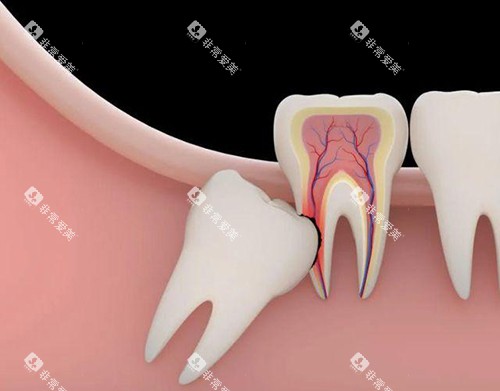

智齿拔除

智齿的生长情况较为复杂,拔除难度差异较大。

如果是正位智齿,拔除价格在200 - 500元左右。

但如果智齿是阻生的,如水平阻生、垂直阻生等,拔除过程较为复杂,可能需要切开牙龈、去除部分牙槽骨等操作,价格会明显升高,一般在500 - 1500元不等。